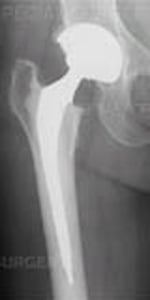

With both traditional hip replacement and surface replacement, the socket is inserted in a similar fashion. The two procedures differ in the way the femur is prepared. Whereas traditional hip replacement involves removing the head and neck of the femur, surface replacement preserves this bone. With a traditional hip replacement, after this bone is removed, a prosthetic ball attached with a stem is inserted within the thigh bone. With a surface replacement, the preserved bone is sculpted to accept a metal cap with a short stem.

Traditional total hip replacement

Hip resurfacing

Image Courtesy of Smith and Nephew